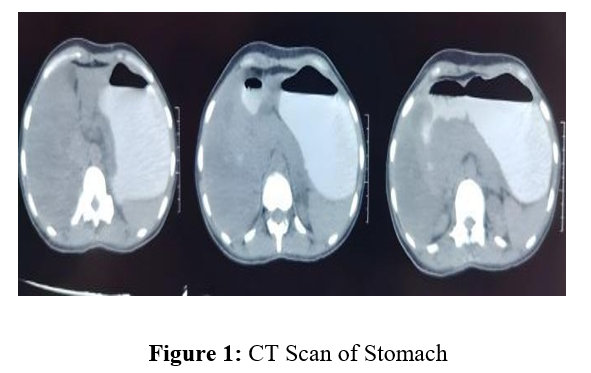

A forty-year-old female came with abdominal pain, vomiting after meals, fever and loss of appetite since six months. She went to a gastroenterologist, where endoscopy revealed ulcers in her stomach, with stricture in duodenum and sigmoid colon. Biopsy from stomach ulcers revealed diffuse infiltrating adenocarcinoma of signet ring phenotype. She was referred to our centre for further management as gastric cancer. On thorough clinical examination, well defined lump were found in both breast with multiple bilateral axillary lymph nodes. There were bilateral cervical, upper, middle, lower jugular and supraclavicular lymph nodes. Sonography also confirmed same finding. Her CECT scan of abdomen revealed circumferential thickening involving ileo – caecal junction and caecum with multiple para-aortic lymph nodes. Bilateral adenexa were bulky and non – enhancing. Lung showed no abnormality.

Our patient had diffuse infiltration of submucosa and muscularis propria giving a picture of linitus plastica in contrast enhanced CT scan, which is the most common pattern of breast cancer metastasis. Diffuse intramural infiltration imitating linitus plastica in gastric metastasis patients was reported to be 78% by Madeya and Borsch.[10] Our findings was consolidated by the findings of Cormeir et al, which concluded that linitus plastica is the most common pattern of involvement in gastric metastasis.[11].